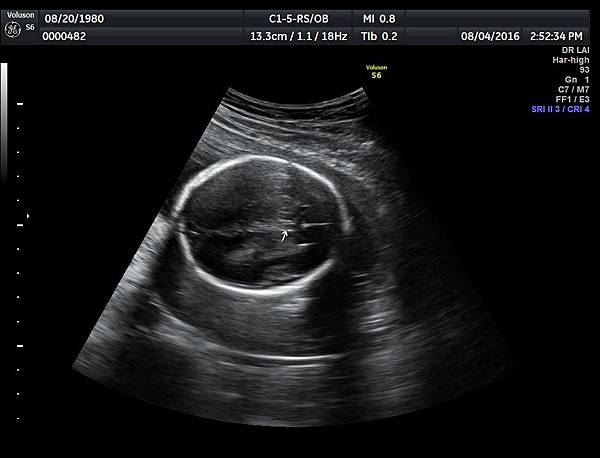

2016年8月4日在執行胎兒高層次超音波檢查時,我發現胎兒腦部的CSP(cavum septum pellucidum)很不清楚(附圖1~4),遇到這種情況,需要仔細評估胎兒腦部的駢胝體,因為CSP的天花板是駢胝體,CSP不明顯時,要合理的懷疑駢胝體沒有發育,或駢胝體下方有長東西(例如lipoma),駢胝體是連接左右大腦的神經纖維所組成。